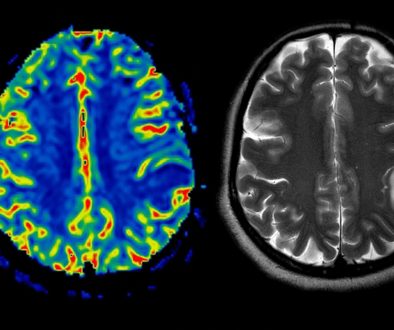

جراحة النخاع الشوكي تعتبر من العمليات الجراحية الحساسة والمعقدة، وتحتاج إلى تخطيط دقيق واستعداد نفسي وجسدي. يُعتبر النخاع الشوكي الجزء الأساسي من الجهاز العصبي المركزي، ويمتد من الدماغ عبر العمود الفقري. أي تدخل جراحي في هذه المنطقة يتطلب عناية فائقة وفهماً دقيقاً لمخاطر الفوائد المحتملة. في هذه المقالة، سنقدم نصائح وتعليمات للمرضى الذين يخططون للخضوع لجراحة النخاع الشوكي.

– الفحوصات المخبرية والاختبارات التصويرية مثل الأشعة، الرنين المغناطيسي، أو الأشعة المقطعية تساعد في تحديد الاستراتيجية المثلى للعلاج.